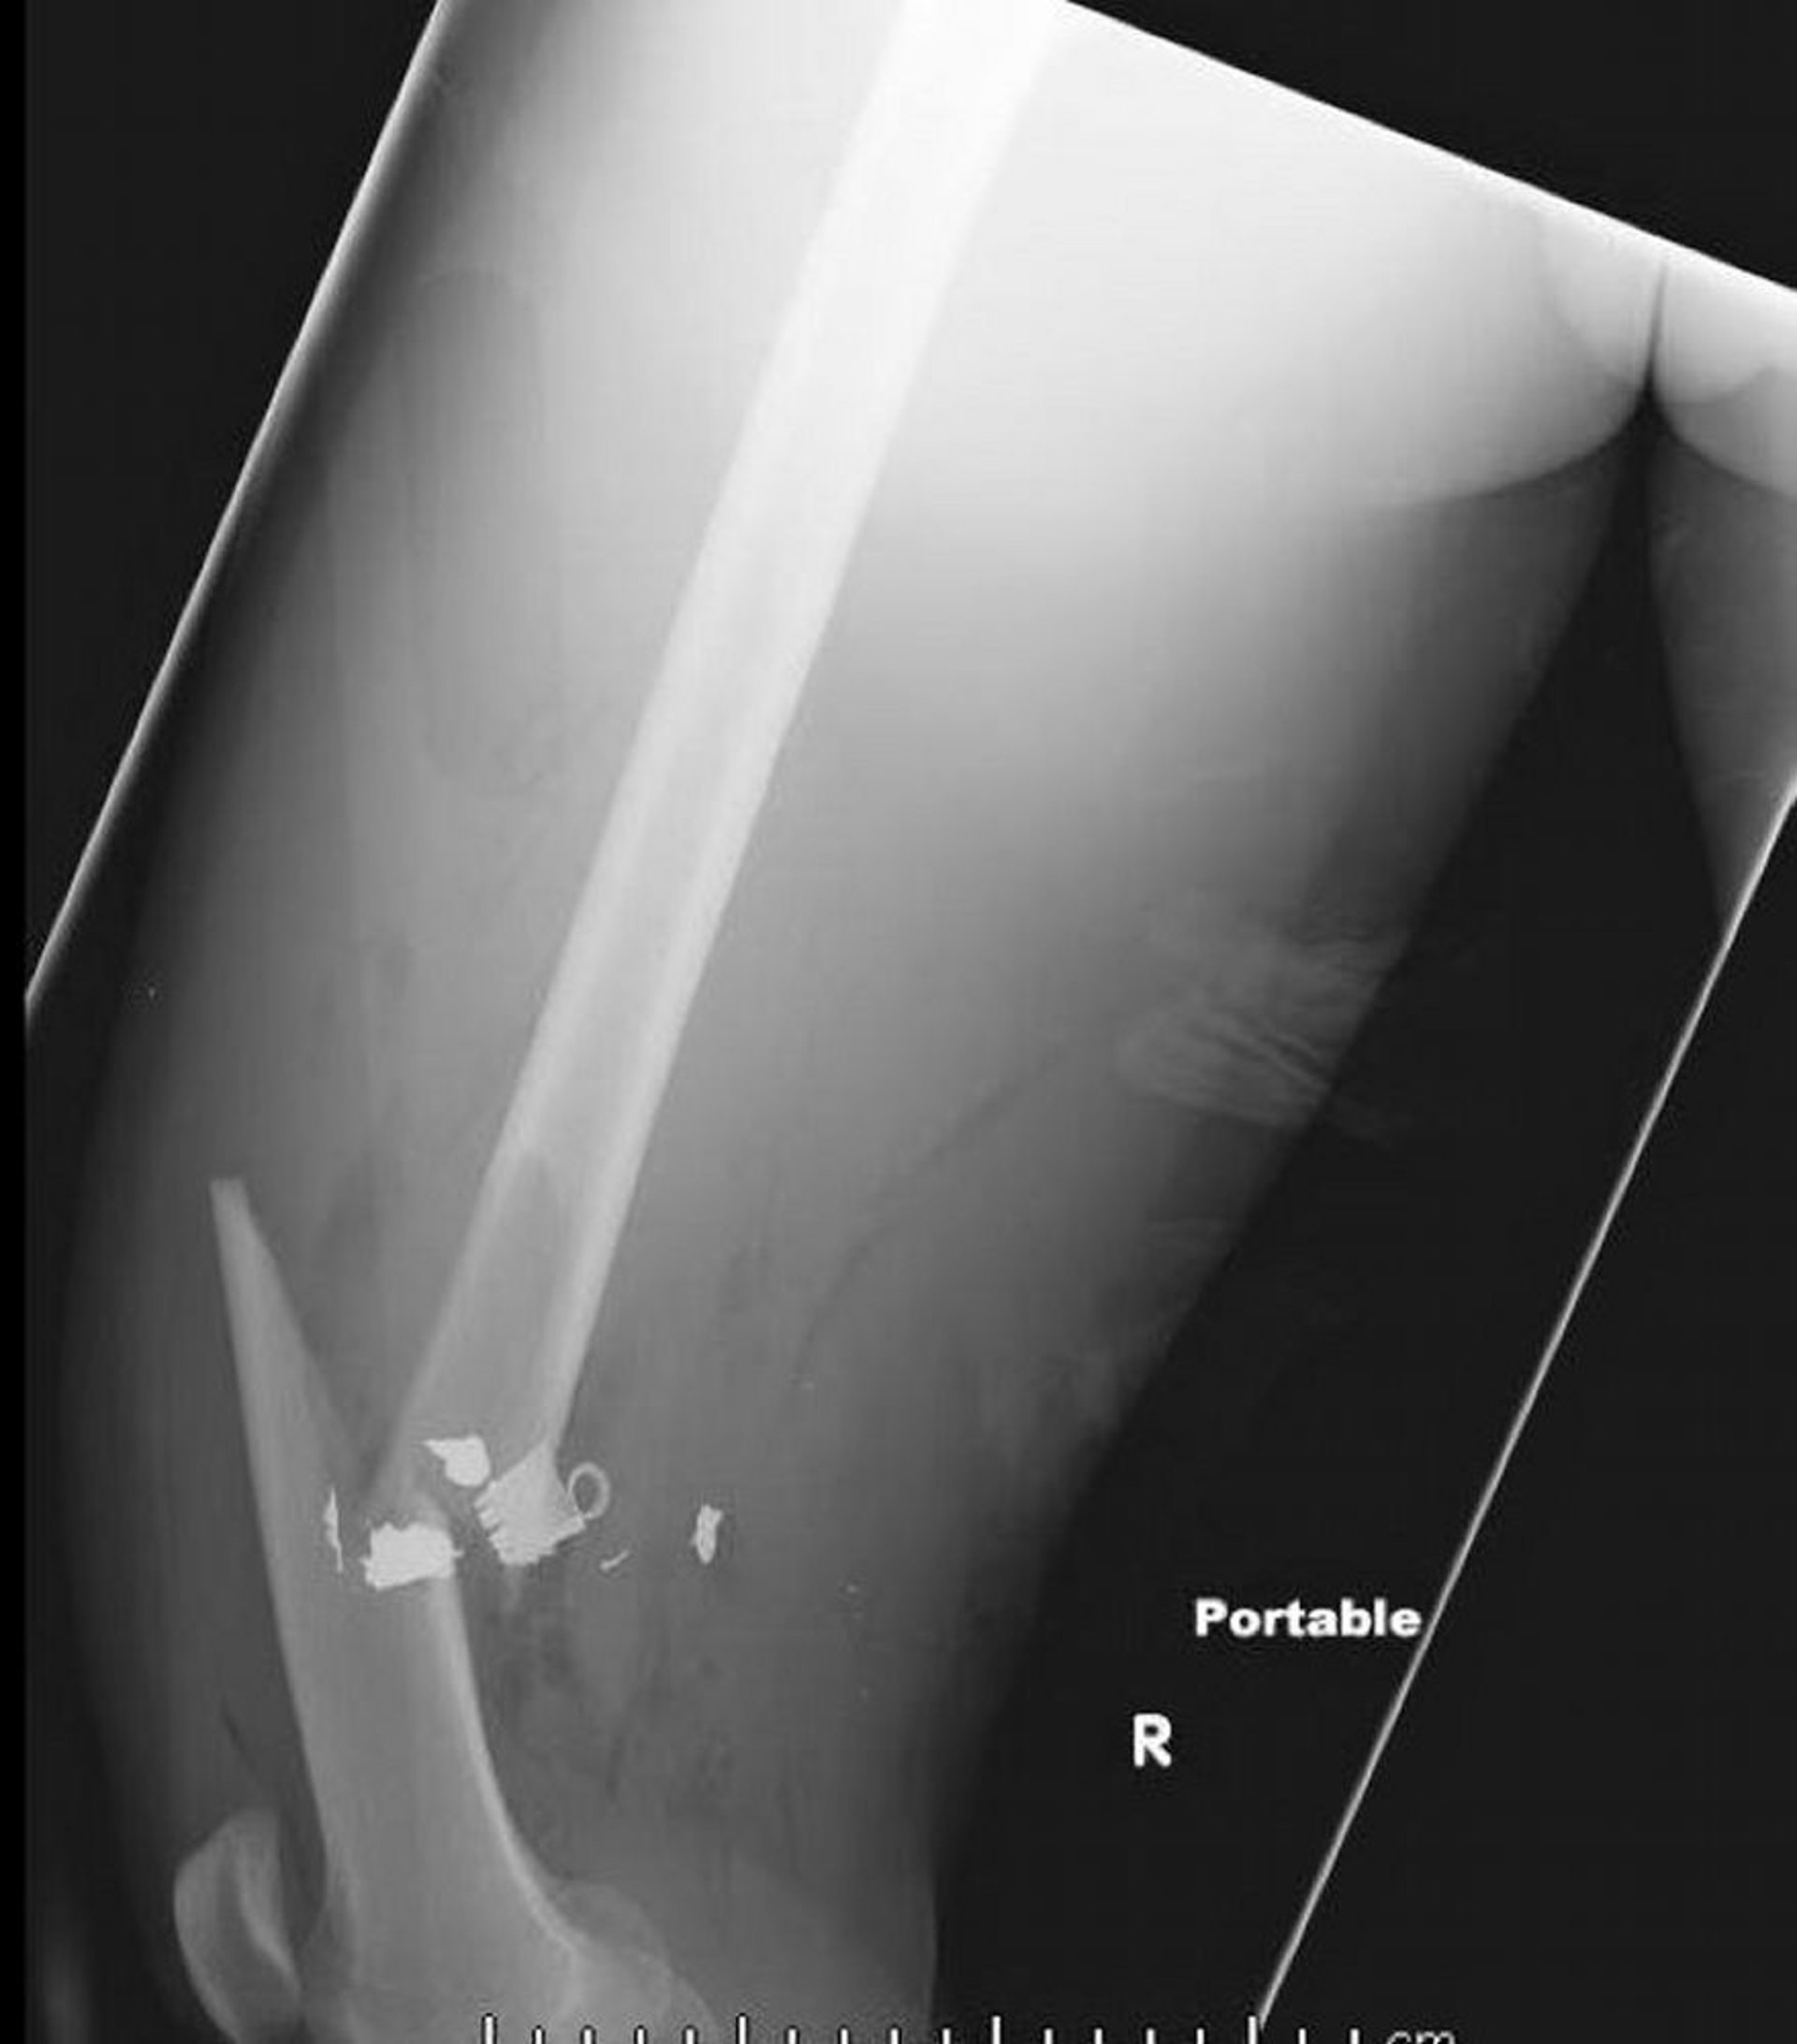

大腿骨骨幹部骨折(2)

この大腿骨のX線側面像には,軟部組織内の空気と金属異物の残存を伴った大腿骨骨幹部骨折が写っている。

Image courtesy of Danielle Campagne, MD.